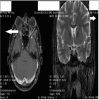

Behcet's disease is a multisystem vasculitis which can be associated with cerebral venous thrombosis (CVT) leading to increased intracranial tension and papilloedema. We report a case of a 17-year-old boy who presented to us with inward deviation of right eye with bilateral disc oedema and on further investigations was found to be Human Leukocyte Antigen (HLA) B5 positive, along with CVT on magnetic resonance venography which further led us to the diagnosis of non-parenchymal neuro-Behcet's.